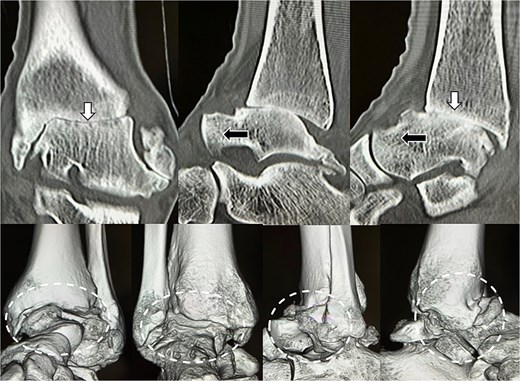

Under arthroscopic visualization, inflamed synovial tissue and degenerated cartilage were removed until healthy subchondral bone was exposed. The tibiotalar joint was anatomically reduced and fixed in neutral alignment with axial compression using three 6.5-mm cannulated cancellous screws inserted from the medial malleolus (Fig. 3).

Immediate postoperative radiograph (X-ray). Ankle arthrodesis using three 6.5-mm cannulated cancellous screws (CCS).